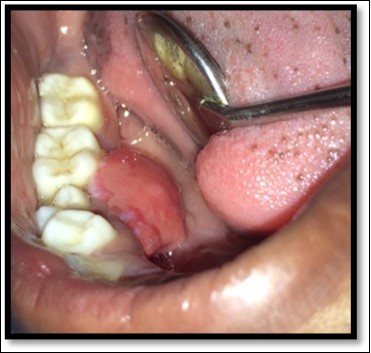

A 13year-old male patient reported to the Department of Pediatric and Preventive Dentistry with a chief complaint of the presence of a ‘lump’ in the lower right back region. The history revealed that the patient had buccal abscess in relation to 85 two months back for three days which reduced on medications. The tooth (85) exfoliated within 1 month and soon after the exfoliation, patient noticed a lump in that region. The lump was painless and increased in size in the last one month. Patient experienced discomfort in speech since the last one week. No abnormality or asymmetry was noted on extra-oral examination. Intraoral clinical examination revealed a painless, fibrous nodular mass with a sessile base in the right lower gingival margin extending from the mesial surface of 44 to distal surface of 45 on the lingual surface, measuring approximately 2 cm in diameter and showing a rough surface and color similar to that of the adjacent mucosa(Figure 1)

Figure 1.Pre operative size and extent of lesion